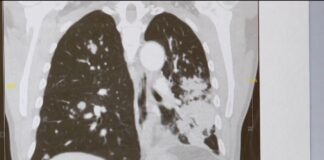

Jorge Manchola, a retired Air Force staff sergeant, was diagnosed with stage 4 lung cancer in 2023. The cancer had spread to his lungs...